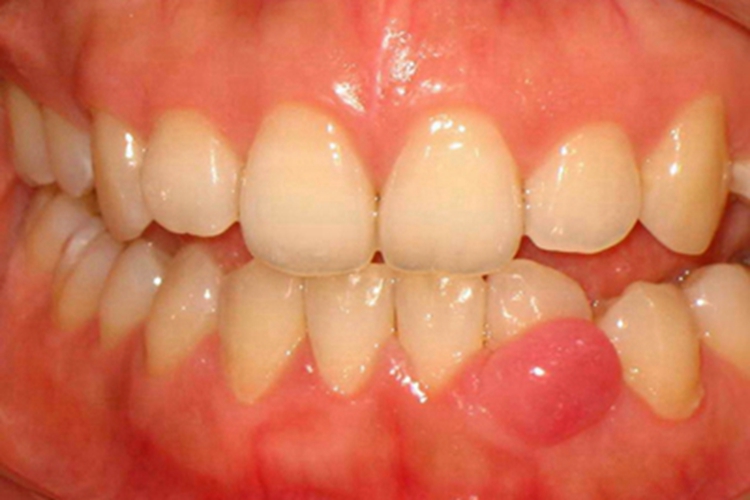

牙龈炎发生后,可见患者口腔下牙龈有一处红肿,表现为明显鼓包凸起,鼓包颜色为亮红色,表面光滑,患者有明显的口腔异物感。一般无痛,可自行消退,也可维持轻度炎症数年。有时因肿胀部位挤压,内侧牙齿可出现移位的情况。

牙龈炎下牙龈一处红肿,主要是口腔卫生差,牙菌斑沉积导致。牙石、食物嵌塞、不良修复体、牙错位拥挤、口呼吸等因素可促进菌斑的堆积,引发或加重此种情况。